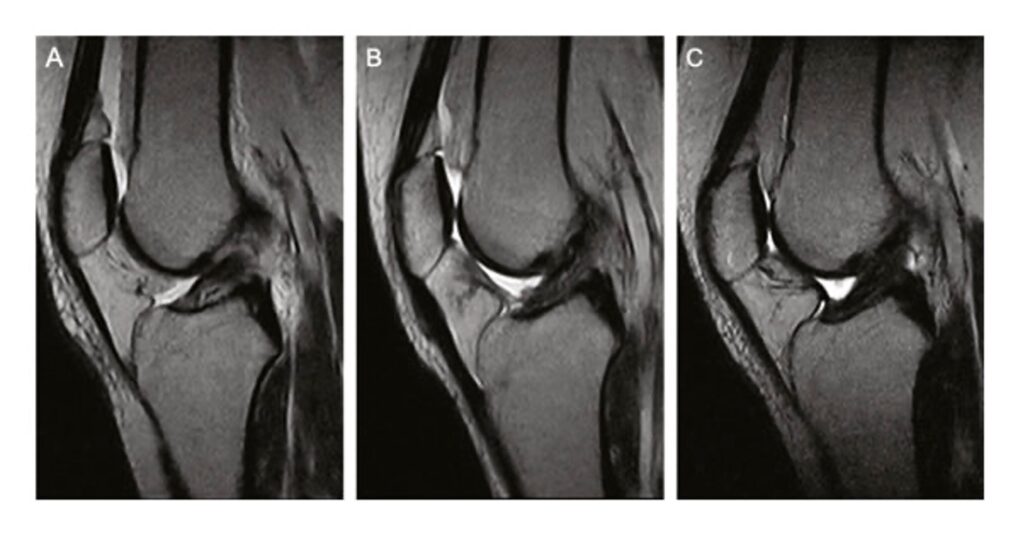

Zusätzlich wird in der modernen Medizin zunehmend Wert auf die Verwendung von bildgebenden Verfahren gelegt, um den Verlauf der Heilung zu überwachen. Die Durchführung von Folge-MRTs kann es den Ärzten ermöglichen, den Fortschritt der Genesung objektiv zu bewerten und gegebenenfalls Anpassungen im Therapieansatz vorzunehmen.

Im Verlauf zeigte sich eine zunehmende Belastbarkeit. Vier Monate nach dem Unfall war Radfahren möglich. Sieben Monate später erfolgte eine Kontroll-MRT.

Dokumentierte Verlaufskontrolle

Die Untersuchung zeigte eine narbige Bandkontinuität und stabile Gelenkverhältnisse.

„Entscheidend ist nicht nur das Bild“, sagt Tkacz.

„Entscheidend ist, ob das Knie klinisch stabil und belastbar ist.“